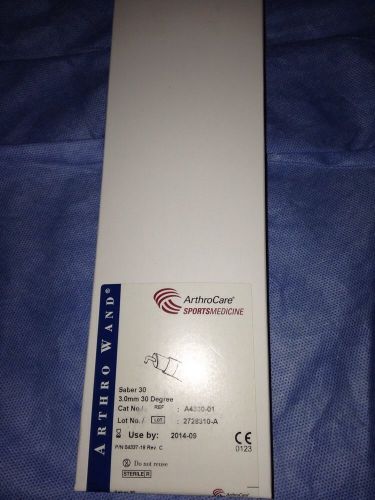

ArthroCare Arthro Wand Saber 30 A4330-01